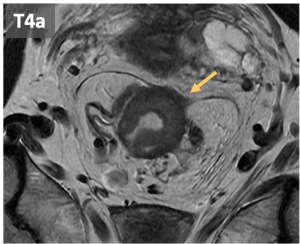

- T4: can be classified in:

- T4a: invasión of adjacent organs